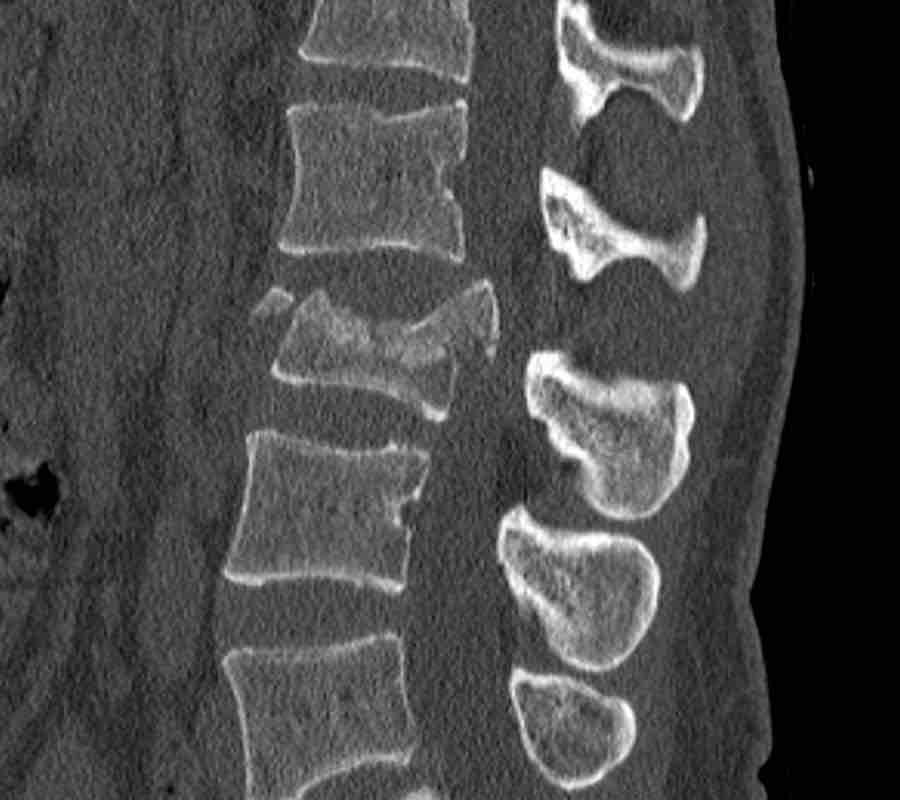

What is the highest AO-type of injury?

Findings

- No C or B injury.

- Fractures of the vertebral body with involvement of both endplates (1+1 points) and posterior wall (2 points).

- In the coronal plane, a sagittal course of the fracture is seen, which is common in burst fractures.

- Bulging of the posterior wall without any other signs of dislocation is the result of the burst fracture.

Therefore no C injury.

Conclusion

Injury type A4

Here more examples of typical burst injuries.

Due to the axial force, the vertebral body is ‘split in half’, therefore a sagittal course of the fracture is common.

Therefore a fracture through the posterior osseous structures is possible in some type A injuries and should not always be regarded as a posterior distraction injury.

This can be confusing sometimes.